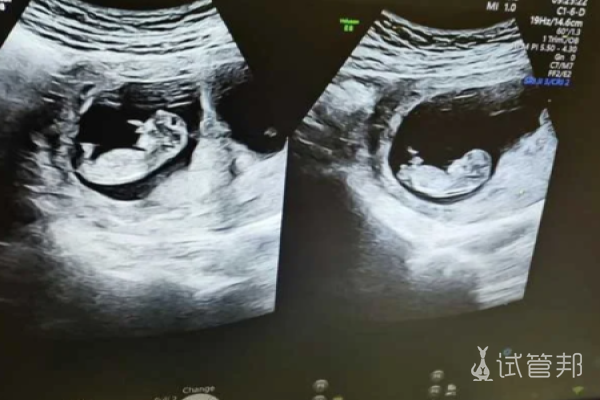

试管怀双胞胎,听起来好像是一段美妙的旅程,但实际上却是一场艰辛的挑战。在我家,多年来没有出现过双胞胎的情况,而由于身体原因,我被告知需要进行试管婴儿受孕。了解到试管受孕可以将两个胚胎放入子宫,但不一定都能成功着床后。

我和丈夫商量后,决定一次做2个胚胎的移植,希望一次成功。但是,试管怀双胞胎真的很辛苦,让我有了更深刻的体会。